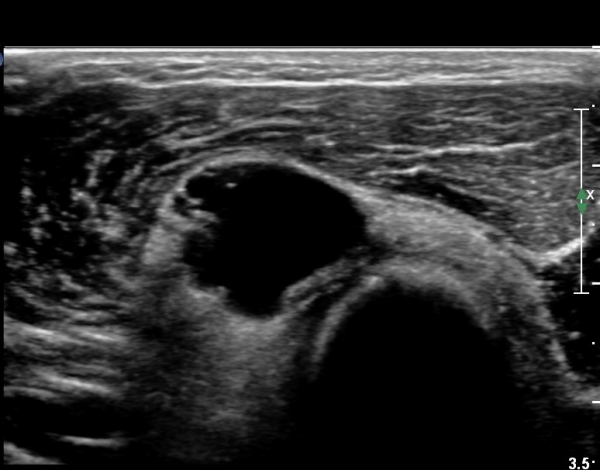

¿ä°ñµÎ ±ÙÀ§ºÎ Ⱦ´Ü¸é°Ë»ç»ó Èİñ°£ ½Å°æ ³»ÃøÀ¸·Î ÀÛÀº ³¶Á¾ÀÌ °üÂûµÈ´Ù(»çÁø 1).